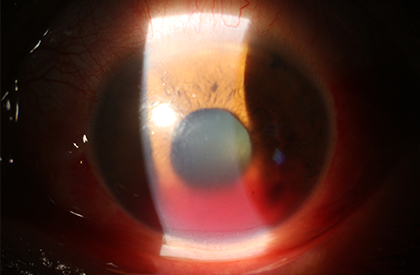

안구와 안와 외상은 시력에 영향을 줄 수 있어 외상 시 바로 정밀하게 검사를 하여야합니다. 안구 외상 시 가장 흔한 전방출혈 시에는 적혈구에 의한 각막염색이나 재출혈, 이차성녹내장이 오지 않는지 주의깊게 경과 관찰하면서 약물로 치료하게 됩니다.

외상으로 인한 전방출혈